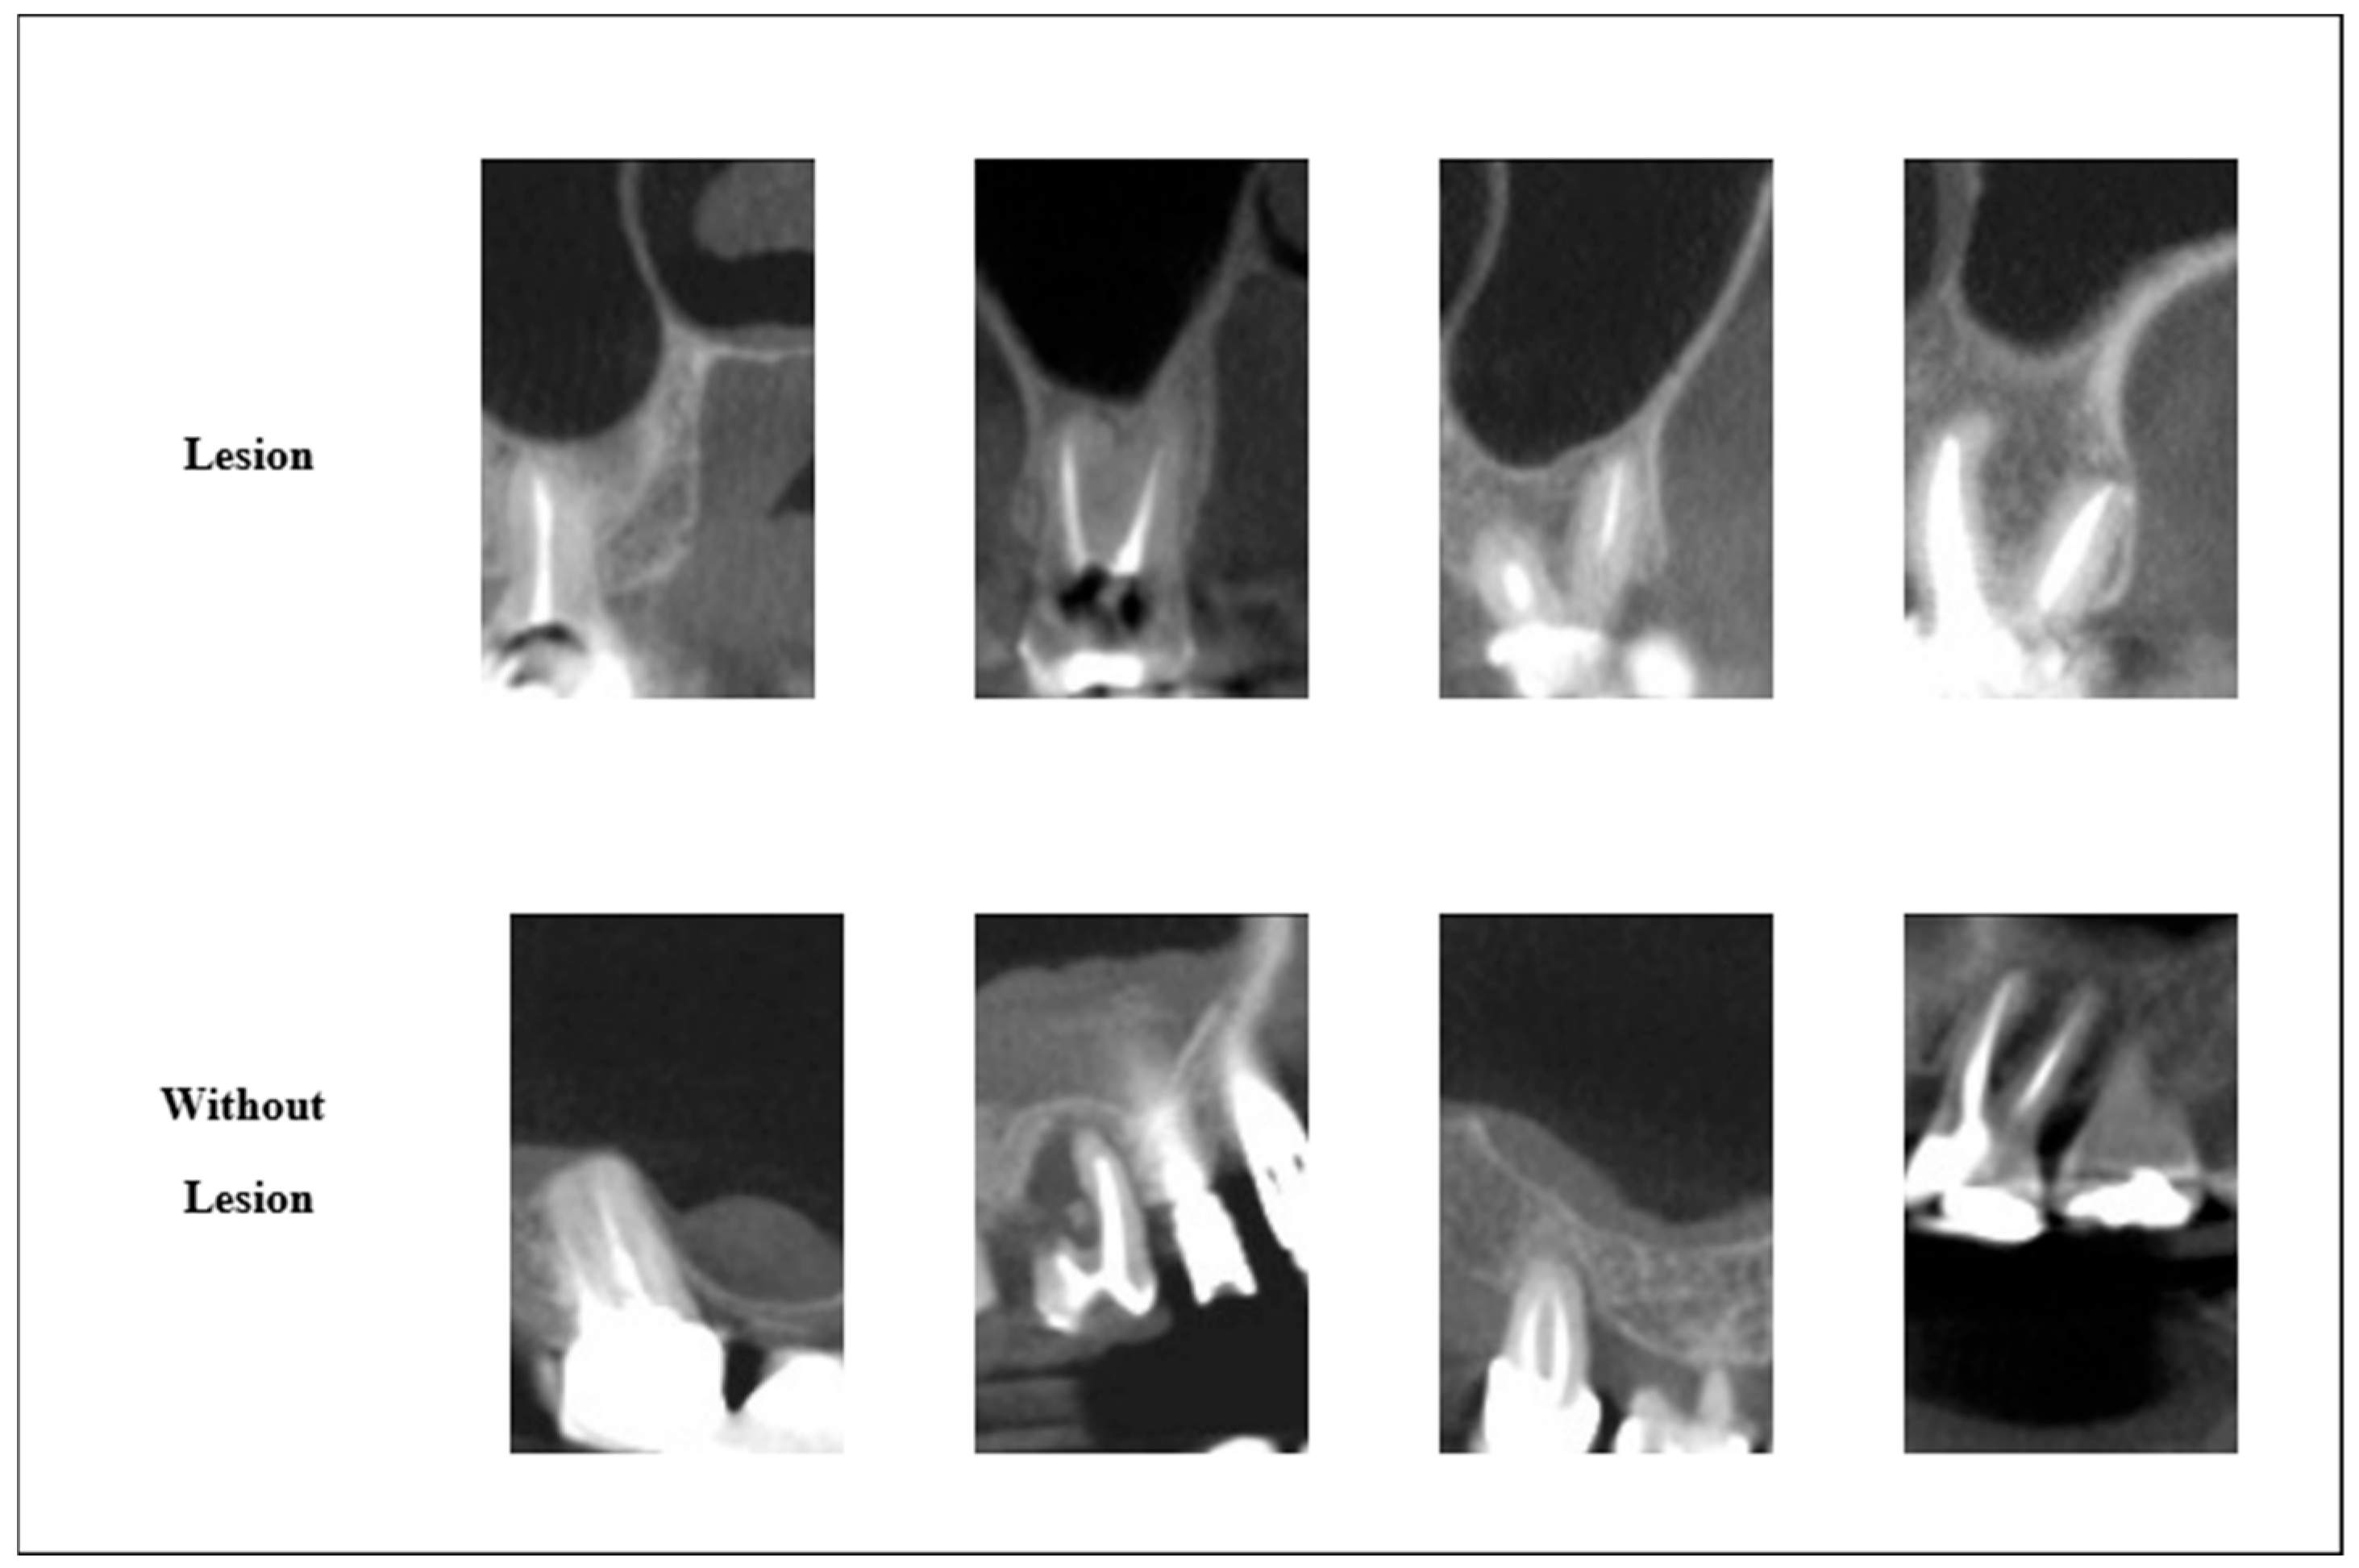

The flow diagram of the 3 basic steps of proposed image processing approach 1 for images with and without lesions is given in Figure 2 and Figure 3.

The enhanced images shown in Figure 2 and Figure 3 were converted into data where sensitive points and boundaries were highlighted.

The image processing approach successfully localized pixel values ranging from 0 to 255. This offers the potential for a powerful feature set for the classification of images with and without lesions.

Figure 2. Stages of implementation of proposed image processing approach on a with lesion image [30].